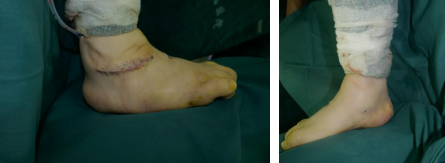

术后

术后第二天,给患者换药时,家长看到孩子的脚形得到了完美的矫正,非常满意。

术后第五天,患者康复良好,准备出院回家。“回去了注意抬高患足,尽可能让她主动活动,让肌肉得到锻炼,康复进度才能加快。”曹广超主任查房时叮嘱家属。